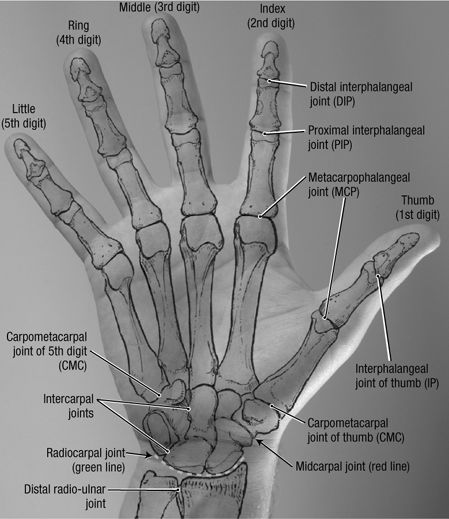

Upper Extremities

Fingers

For 2nd–5th digits. Specifically to look at 1 finger for

trauma, foreign body, or localized mass. A marker should be applied,

particularly on the lateral projection. Consider US for radiolucent

foreign body. Consider MRI or US for mass or tendon lesion/injury.